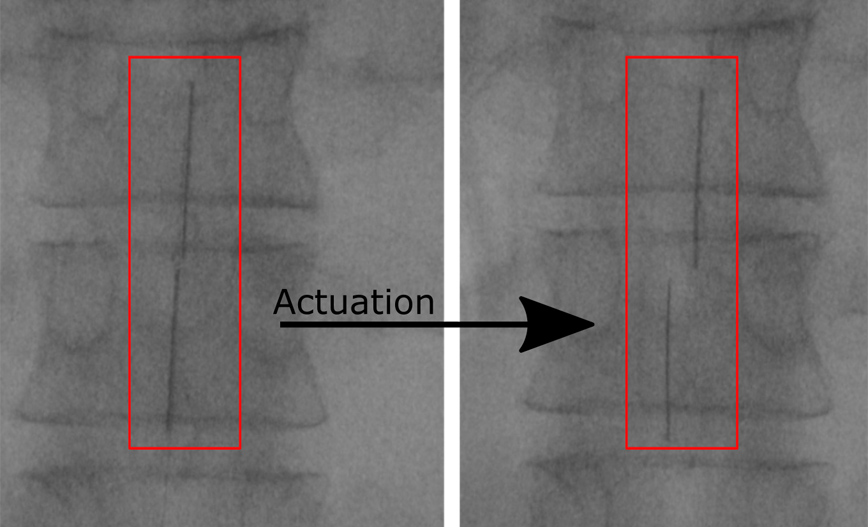

Όταν βρεθεί μέσα στο σώμα, η συσκευή φουσκώνει με νερό ή αέρα και ξετυλίγεται σαν ένα μικρό στρώμα που καλύπτει ένα μεγάλο τμήμα του νωτιαίου μυελού. Όταν συνδέεται με μία γεννήτρια παλμών, τα ηλεκτρόδια της συσκευής αρχίζουν να στέλνουν ηλεκτρικά σήματα στον νωτιαίο μυελό, μπλοκάροντας τα σήματα του πόνου.